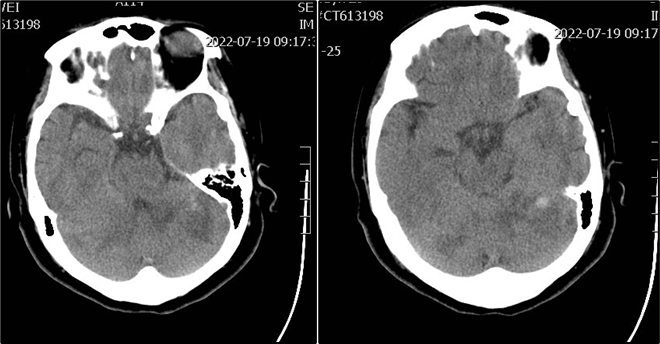

术后影像及检查

术后正位造影。

术后侧位造影。

术后第一天复查头颅CT。

导丝怎么扩【载药时代 球扩天下】NOVA DES®颅内药物洗脱支架在基底动脉近端重度狭窄的应用—西安市中心医院使用体会一例!_https://www.jmylbn.com_新闻资讯_第8张

术后1月随访(随访日期:2022年8月24日):

术后1月患者NIHSS 2分,mRS 1级;头颅MRI示脑干、双侧小脑、右侧枕叶多发陈旧梗死;CTA示基底动脉近端管腔支架植入术后,未见明显狭窄。